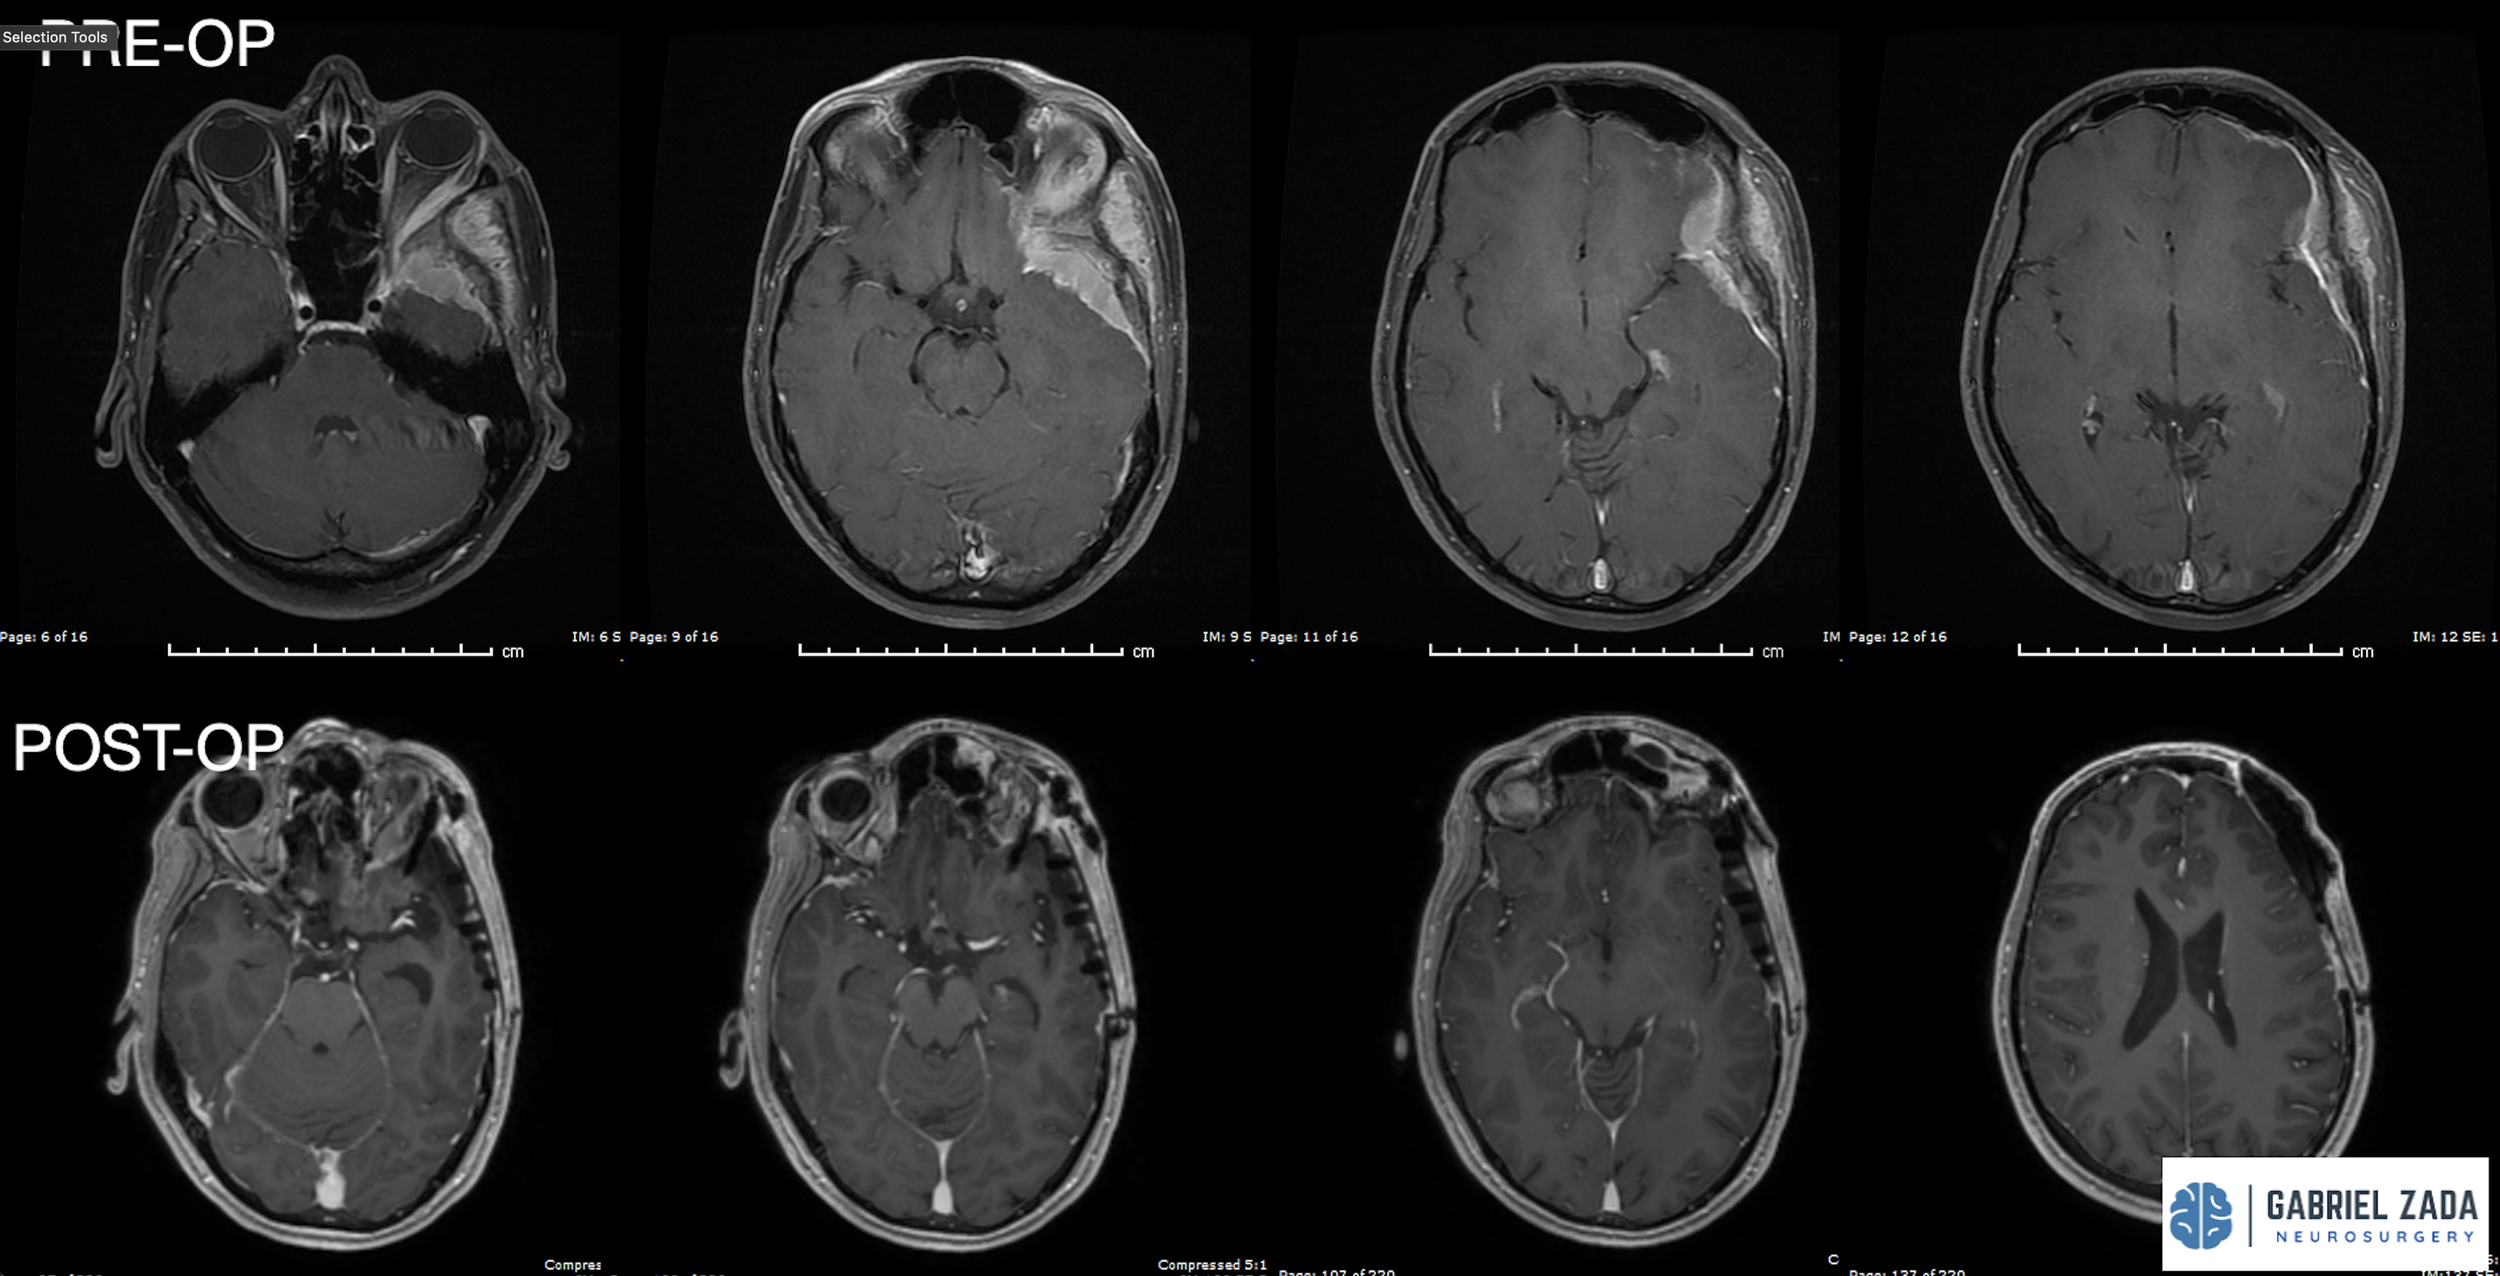

Explore this comprehensive gallery featuring pre‑ and post‑operative imaging of patients with skull‑base tumors treated by Gabriel Zada, MD, MS, FAANS, FACS. These cases highlight Dr. Zada’s expertise in advanced neurosurgical techniques and outcomes.

*Representative cases shown for educational purposes. All images de-identified. Individual results vary.